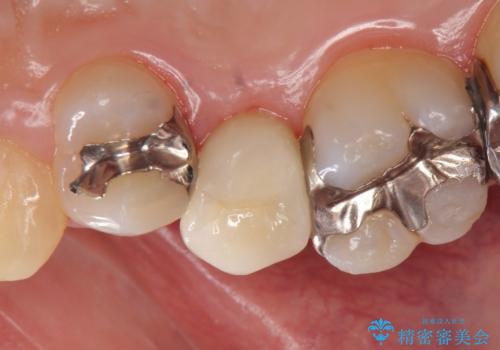

- 頬側から見たとき右上5番目の銀歯が気になるので、オールセラミッククラウンによる補綴を行った症例です。

今回用いたオールセラミッククラウンはジルコニアフレームという白い素材の上にセラミックを盛っているため、審美性が非常に高いのが特徴です。

また、ジルコニアは人工ダイヤモンドの材料にも使われているほど高い強度を持っており、そのためオールセラミッククラウンは審美性だけでなく、奥歯やブリッジの補綴も可能とするクラウンです。